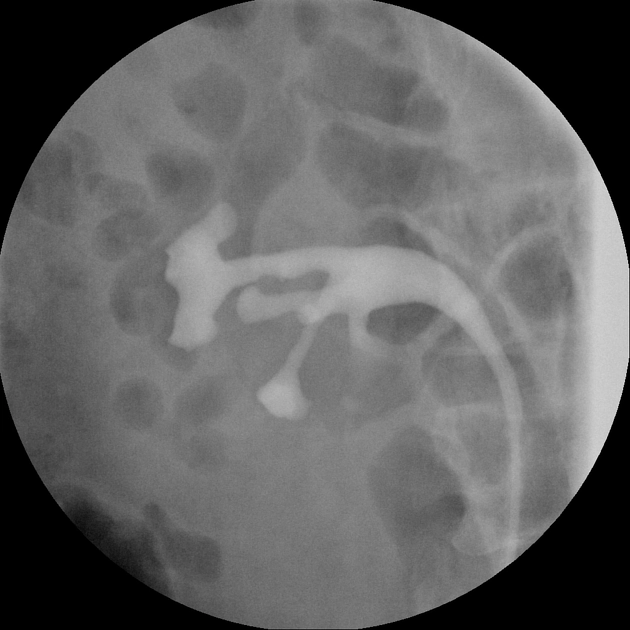

Viêm niệu quản dạng nang (Ureteritis cystica)

Giả túi thừa niệu quản (Ureteral pseudodiverticulosis)